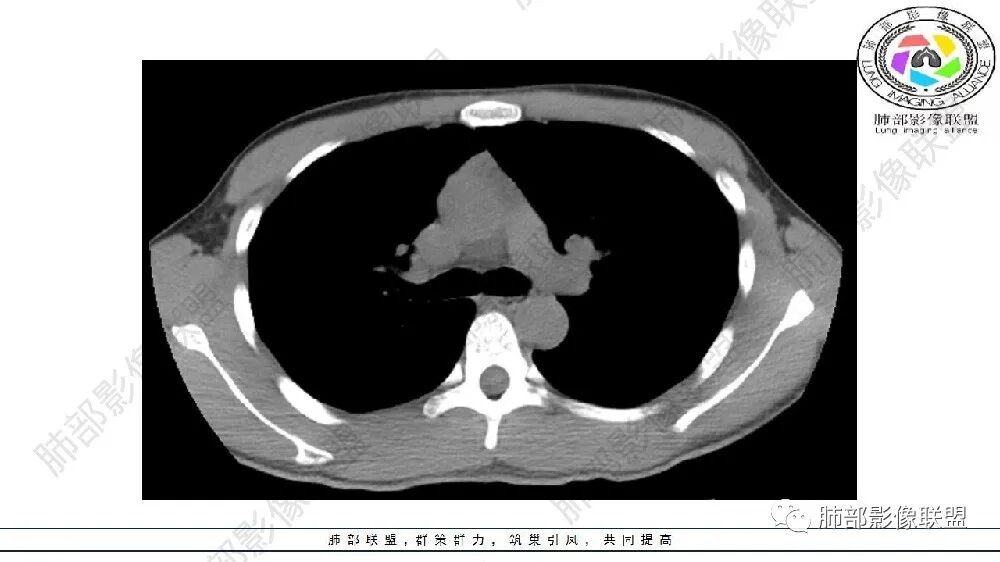

左肺下叶多发大小不等囊腔伴周围磨玻璃影,可见血管增粗,似与胸主动脉相连,考虑肺隔离症,鉴别CPAM。

左肺下叶病变气体潴留,血管增粗,体积缩小,慢性炎遗留表现,考虑局部反复感染,气道通畅,考虑血管病变,肺静脉畸形,肺隔离症?

左肺下叶多发囊腔、斑片、索条(粗大扭曲的血管?)降主动脉左侧有血管影?首先考虑肺隔离症,建议增强扫描,鉴别囊腺瘤样畸形

左肺下叶多发囊腔,粗大血管影,隔离征可能,鉴别气道畸形。

年轻男性,左肺下叶肺动脉明显增粗特点(与对侧比较,降主动脉旁胸膜下分布粗大血管征、左肺下叶肺气囊腔和磨玻璃影,首选肺隔离征,与血管畸形鉴别,病理生理特点:体循环异常分支(压力高)与左肺下叶肺动脉成异常交通。血管血流倒灌左肺下叶表现。

青年男性,左肺下叶多发囊腔伴磨玻璃影,并见增粗血管影,考虑肺隔离症。

可见囊状影、管状影,附近血管明显增粗,似乎与肺动脉不相连

1、需要明确血管与主动脉关系,如果相连--隔离症

主要观察左下叶病灶,应该是做过手术或明确了血管与主动脉关系,就目前的表现而言还是更支持隔离:肺动脉、支气管分支似乎没进入病灶区,这是隔离或体动脉供血的特点。囊腺瘤样畸形,按理肺动脉及支气管照样进入这个区域才对;需要重建观察这些血管、支气管才好明确